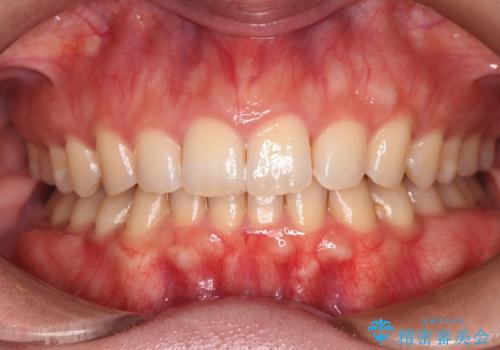

【インビザラインとワイヤー矯正】がたつきと噛み合わせを改善!